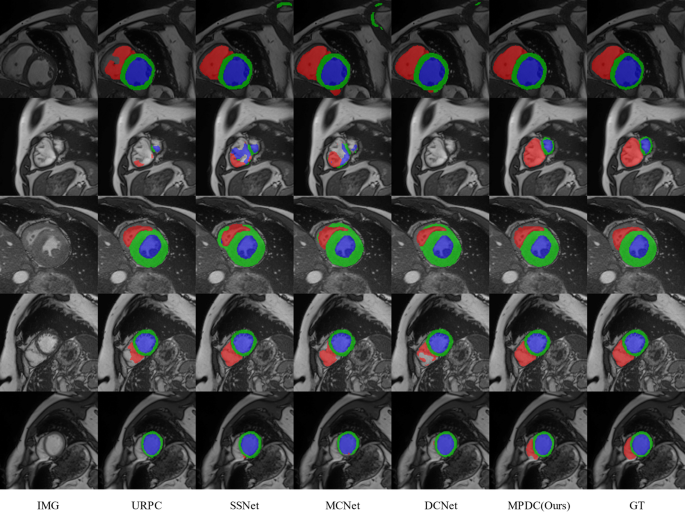

We also provide a visual comparison of the above semi-supervised methods using 7 labeled examples on the ACDC dataset. As shown in Fig. 4, our method can generate sufficiently accurate segmentation results for different slices of left ventricle (LV), right ventricle (RV), and myocardium (Myo). Compared to other semi-supervised methods, our approach exhibits more accurate segmentation capability in terms of boundary segmentation, which also proves the effectiveness of our multi-perspective collaborative learning strategy. Other semi-supervised segmentation methods produce inaccurate results to varying degrees when segmenting the above three regions. And our method can effectively ameliorate this problem, thus obtaining more anatomically realistic results.

To visualize the effect of prostate segmentation in the PROMISE12 dataset, we also perform a visual comparison of the semi-supervised methods listed in Table 2. As shown in Fig. 5, the edges of the prostate in the PROMISE12 dataset are blurred and have low contrast with the background region, making it more difficult to segment. Other semi-supervised segmentation methods are ineffective in segmenting the prostate, with some degree of under- or over-segmentation. However, our method compensates for this deficiency to some extent by introducing a Perspective Fusion Module (PFM), which can greatly improve the segmentation accuracy. Also, our proposed multi-perspective collaborative learning mechanism can improve both the interior and edges of the segmented anatomy.